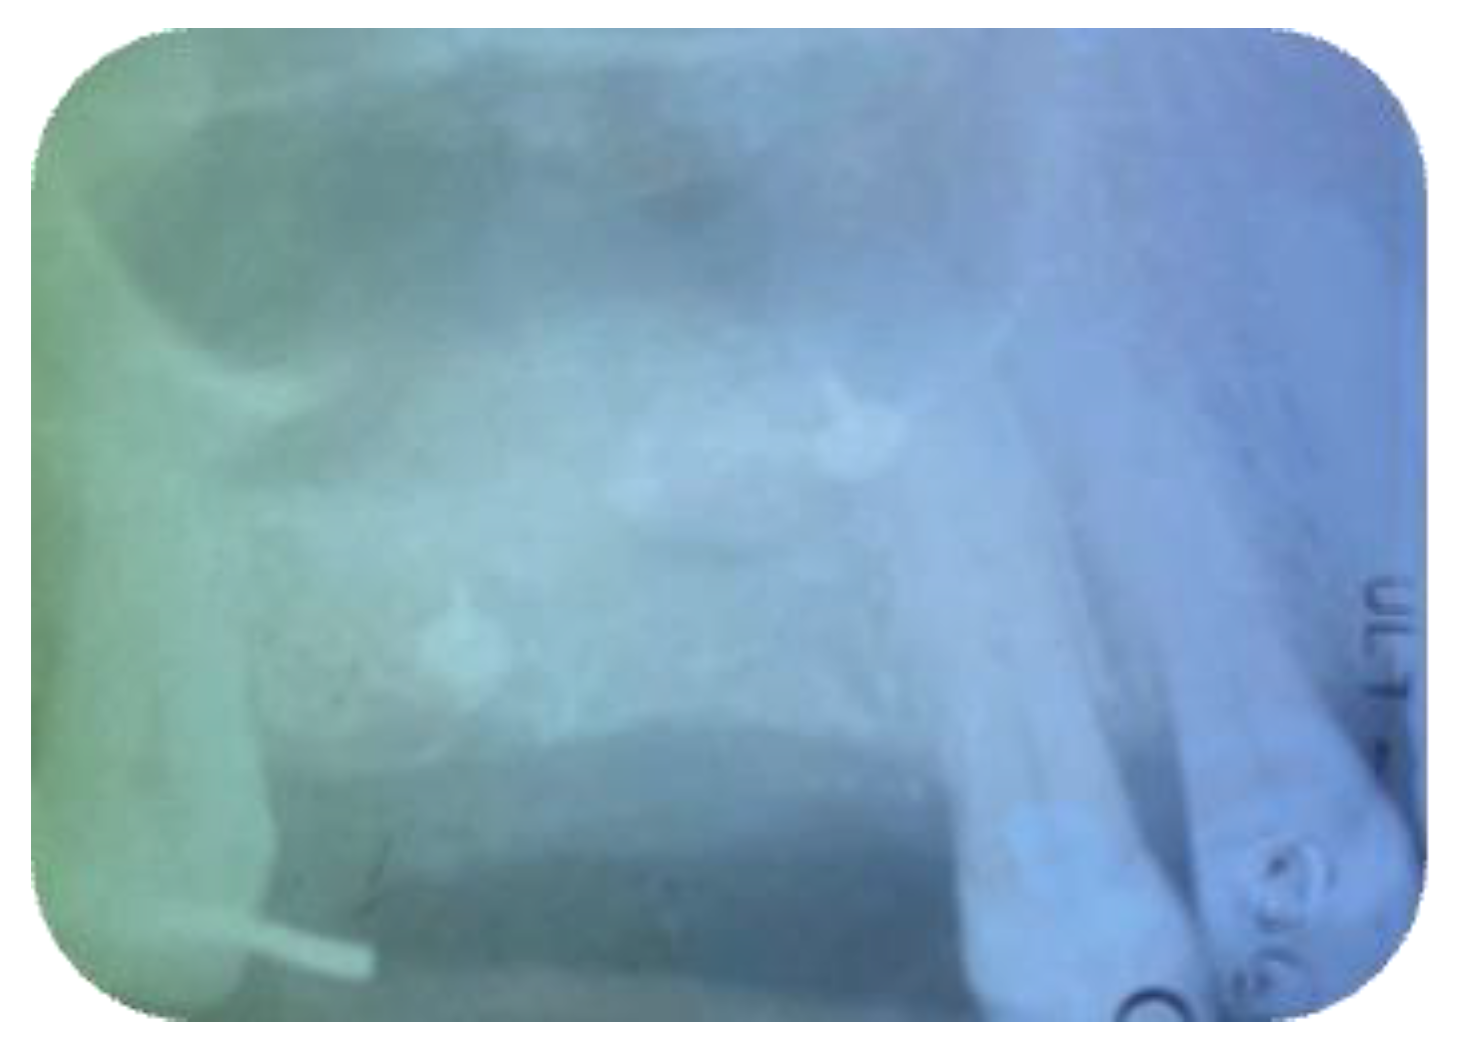

2.1. Surgical Procedures